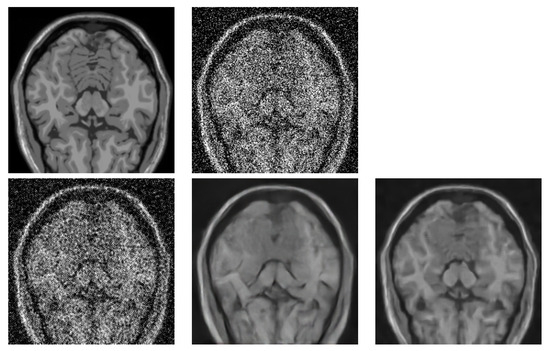

- Application of parallel version of BM4D algorithm to many-core architectures and combination of multi and many-core HW and proving the scalability tests.

- Comparison of the algorithm with DL-based approaches.

- Testing the algorithm as a pre-processing stage before volume rendering.